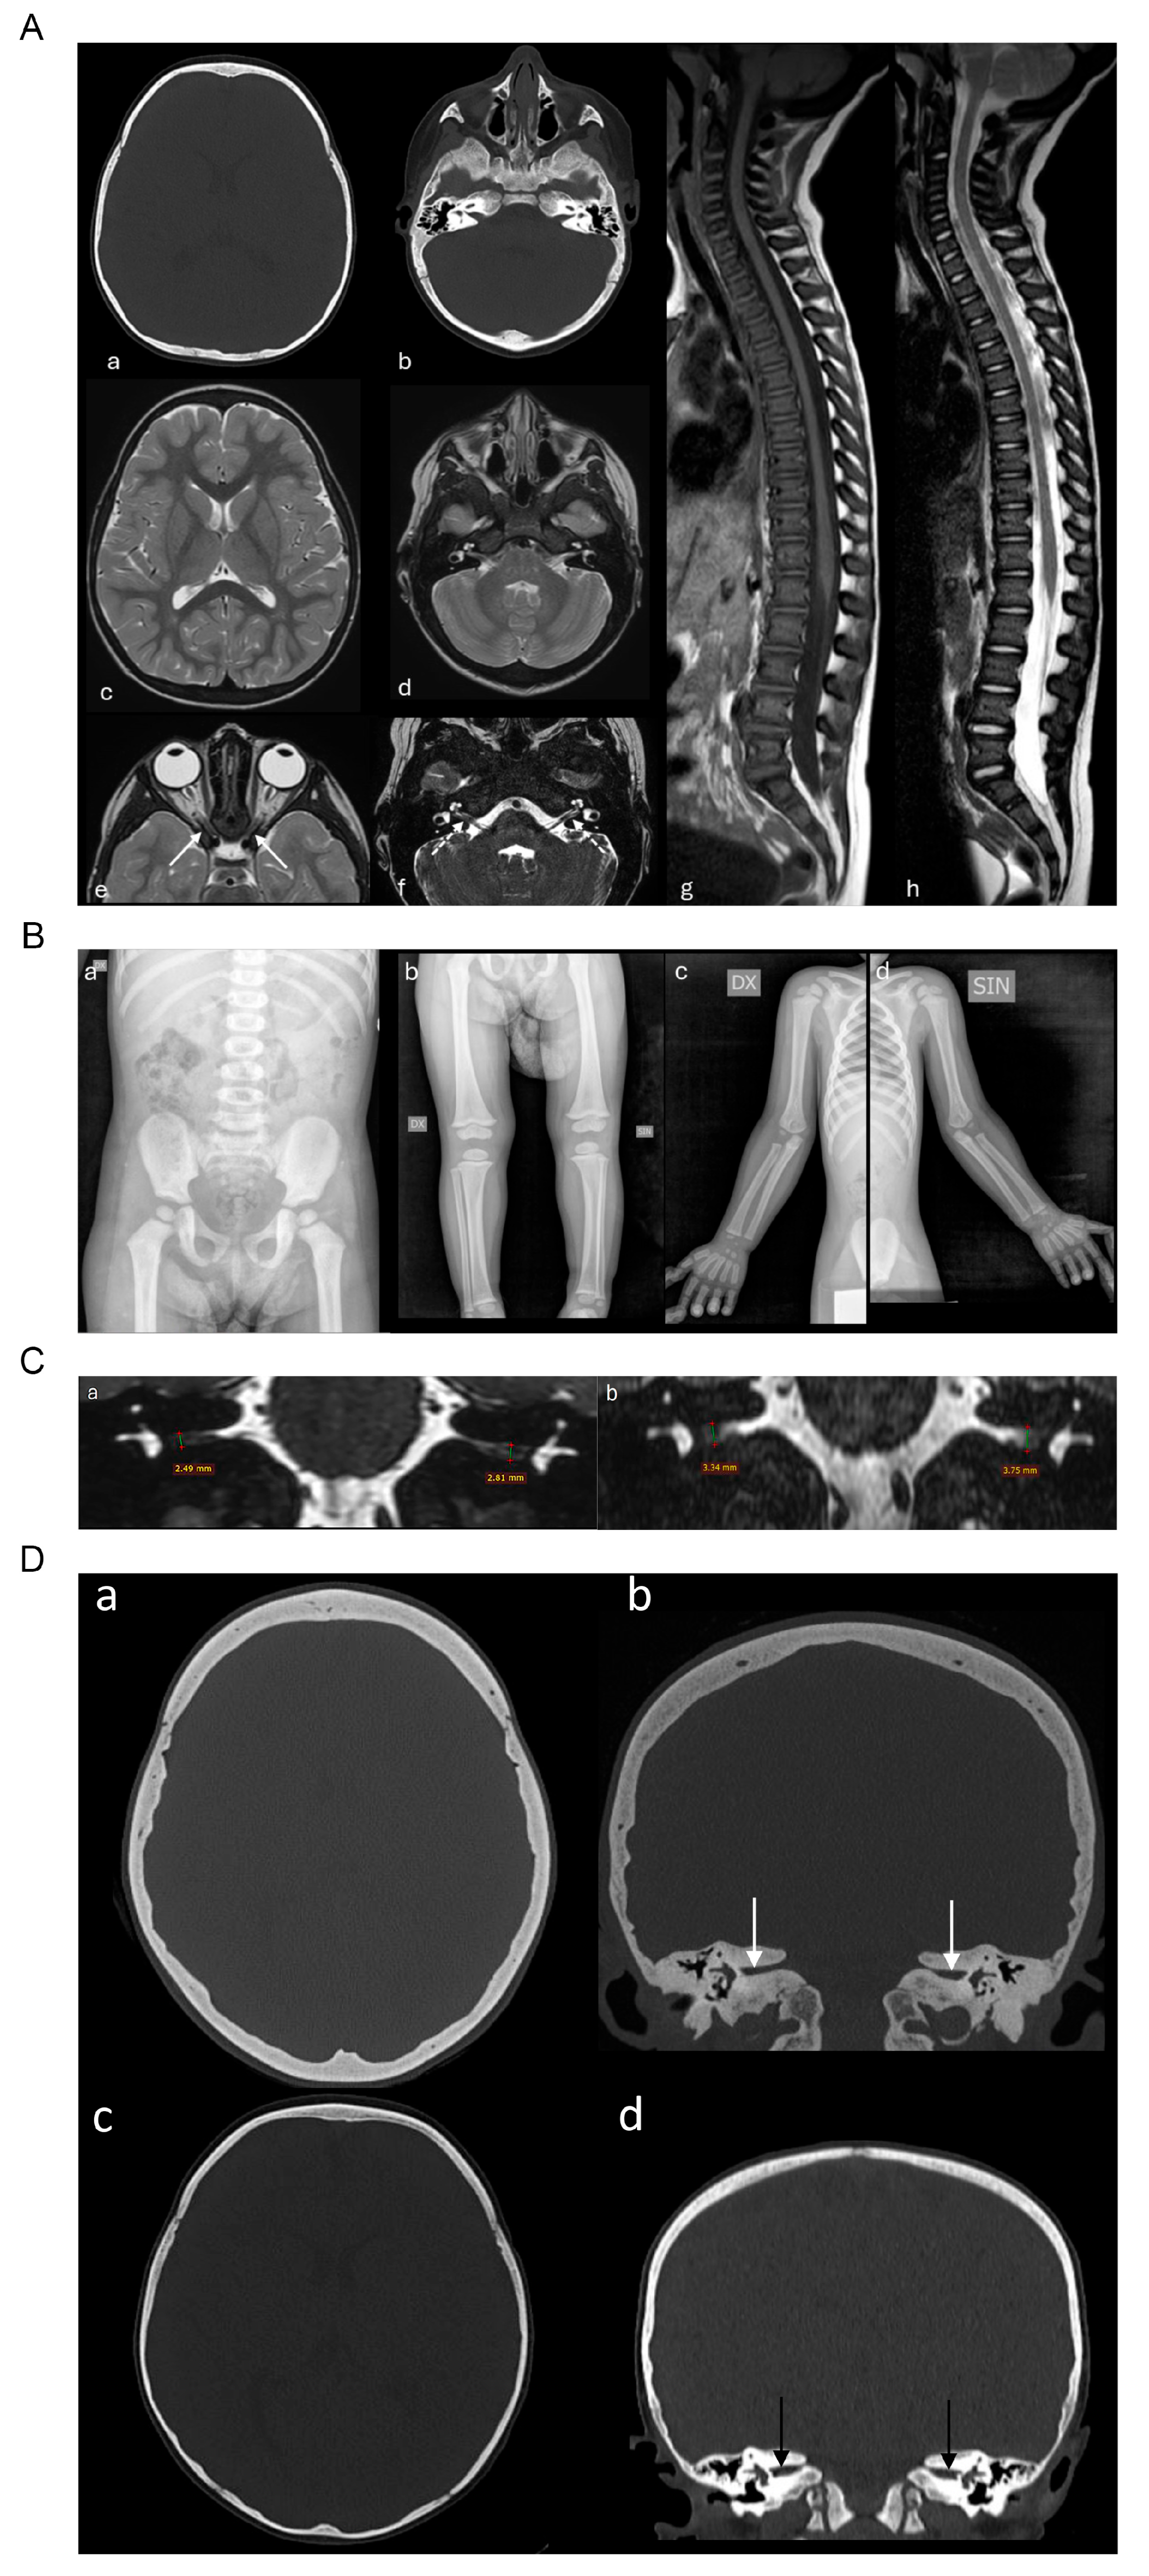

2.1. Case Report

2.2. Genetic Analysis